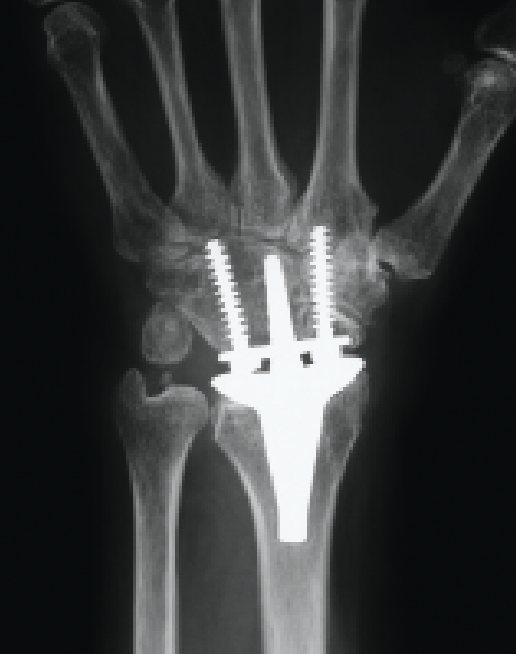

4th generation Universal 2 / Remotion implants

- ball and socket design

- distal radius implant: uncemented porous coated distal radius

- carpal implant: uncemented + screw fixation

- UHMWPE interface